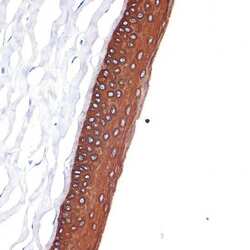

Immunohistochemistry

MA5-42701 IHC